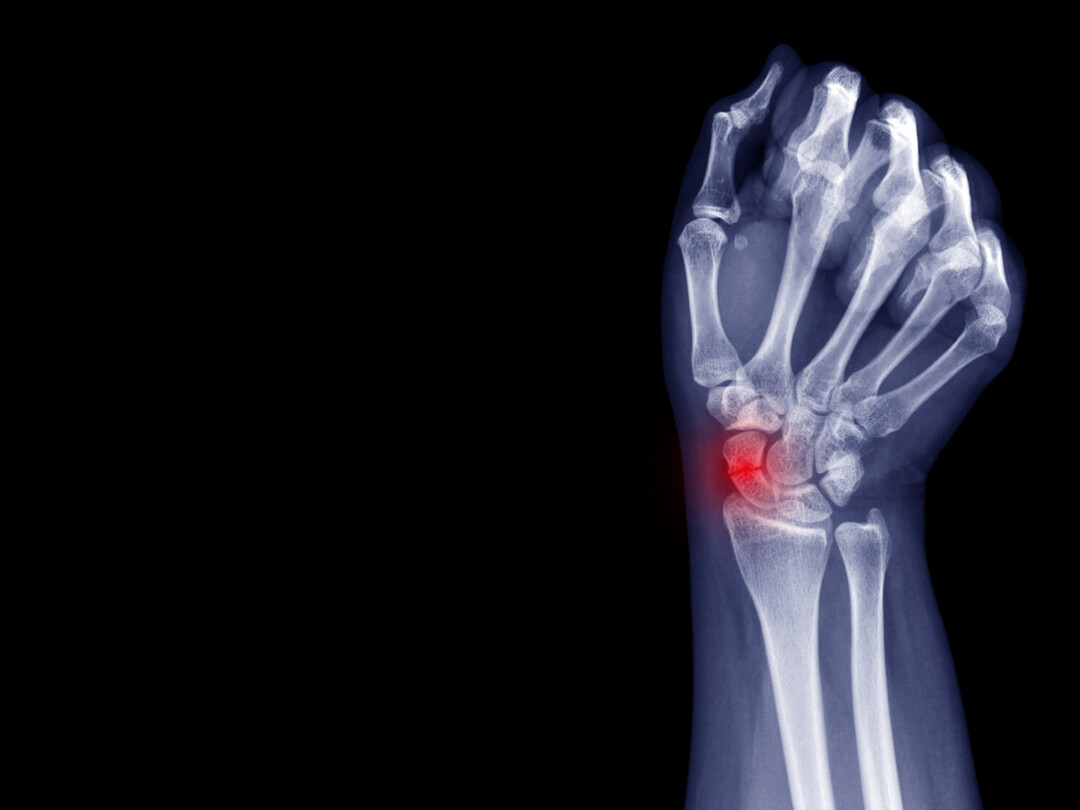

Drukverband bij verdenking scaphoïdfractuur

Röntgenfoto van pols

Bij patiënten met een klinische verdenking op een scaphoïdfractuur en een initieel normale röntgenfoto wordt – conform de Nederlandse richtlijn – de pols geïmmobiliseerd met gips. Dit om te voorkomen dat een onbehandelde fractuur niet goed heelt, met mogelijk posttraumatische artrose tot gevolg.